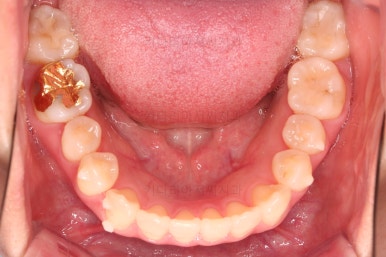

4. 마무리

철사교정과 마찬가지로 앞니쪽에 유지장치를 구성하고 치료를 종료합니다.

매우 가지런해졌고요.

맞물림도 좋아졌고, 중앙선도 잘 맞춰졌습니다.